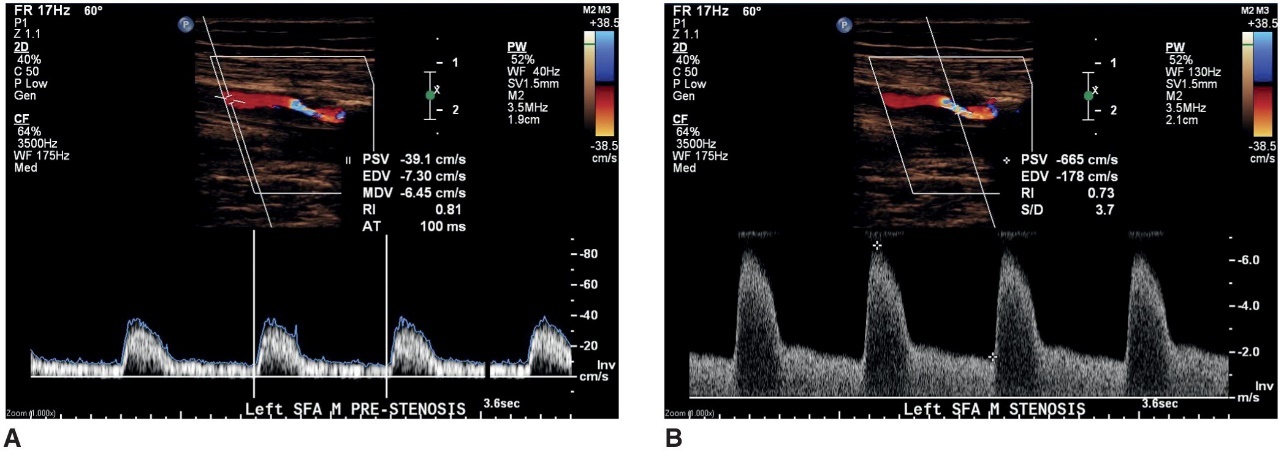

when disease is present (stenosis)

velocities and waveforms should be recorded proximal to the stenosis, in the stenosis, and distal to the stenosis

a doppler waveform taken proximal to a stenosis

what does image A represent

a doppler waveform taken at the area of maximum velocity shift within a stenosis

what does image B represent

a doppler waveform distal to a stenosis documenting poststenotic turbulence

what does this image represent